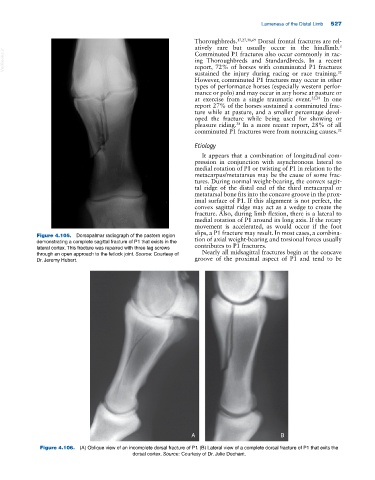

Figure 4.105. Dorsopalmar radiograph of the pastern region tion of axial weight‐bearing and torsional forces usually

demonstrating a complete sagittal fracture of P1 that exists in the

lateral cortex. This fracture was repaired with three lag screws contributes to P1 fractures.

through an open approach to the fetlock joint. Source: Courtesy of Nearly all midsagittal fractures begin at the concave

Dr. Jeremy Hubert. groove of the proximal aspect of P1 and tend to be

Figure 4.106. (A) Oblique view of an incomplete dorsal fracture of P1. (B) Lateral view of a complete dorsal fracture of P1 that exits the

dorsal cortex. Source: Courtesy of Dr. Julie Dechant.